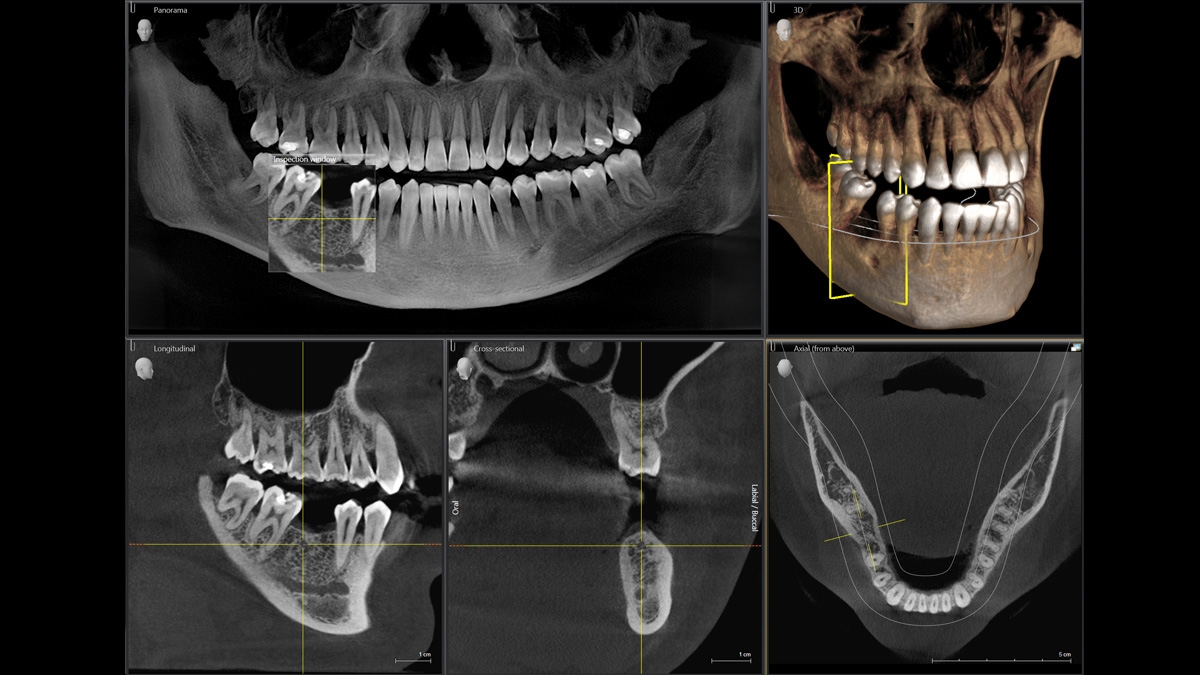

Диагностика последнего поколения, идеально решающая задачи рентгеновского обследования независимо от размеров клиники. Поля изображения зависят от определенной клинической картины, поэтому специалистам так удобно работать с ORTHOPHOS SL 3D. Данная установка делает объёмные картинки для одиночной реставрации в 3D качестве полностью всей челюсти такого размера, которого требуется.

Планирование одиночной реставрации, эндодонтические исследования и пр. – для этого специалист может выбрать объёмные варианты 8 х 8 см или 11 х 10 см, также предлагается объём 5 х 5,5 см. Снимки в HD-качестве, стандартные настройки или выбор объёма обследования в зависимости от диагноза — всё это врач получает в отличном качестве, а для пациента излучение в районе исследования минимально.

С технологией SL можно за один сеанс получить огромное количество снимков. Те из них, где фокусировка наиболее чёткая, автоматически соединяются. В итоге одна процедура — снимки челюсти полностью в самом лучшем качестве. Даже нестандартные случаи не станут помехой в обследовании. К примеру, при ретинированных зубах уже после того, как снимок сделан, нужную область можно выделить подробнее, и в ещё одном рентгене необходимость отпадает.

Модернизированный сенсорный экран Easypad с понятным и удобным интерфейсом позволяет выставить наилучшие параметры контрастности и разрешения. Систематизация данных по диагностике становится значительно удобнее и проще с ПО обработки изображений SIDEXIS 4, ORTHOPHOS.

1. Двух-и трёхмерные снимки совмещаются в одной программе

2. В одном окне можно сравнивать разные 3D-результаты